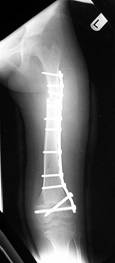

Pre Op

X-ray (Left femur)

osteolytic lesion

(?) osteosarcoma

Post Op

Graft taken well

1cm shortening

of left femur

ROM : 0- 110’